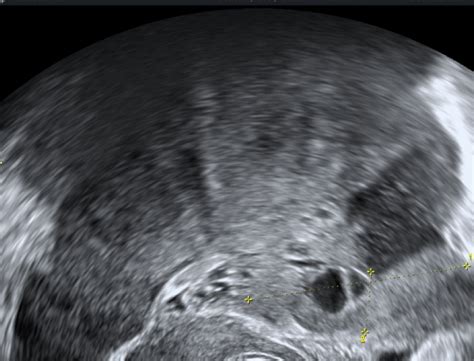

Sam poseg je minimalno invaziven in traja v povprečju 15 do 30 minut. Izvede se na ginekološkem stolu, pogosto v manjši operacijski sobi, ki je povezana z laboratorijem. Postopek poteka skozi nožnico, kjer ginekolog specialist najprej opravi pregled in čiščenje. Med posegom se z ultrazvokom vodi tanka igla skozi steno nožnice v jajčnik, kjer se folikel prebode in se iz njega aspirira folikularna tekočina, ki se nato zbere v epruveti. Po končanem postopku ženska nekaj časa ostane v sobi za okrevanje pod nadzorom medicinskih sester.